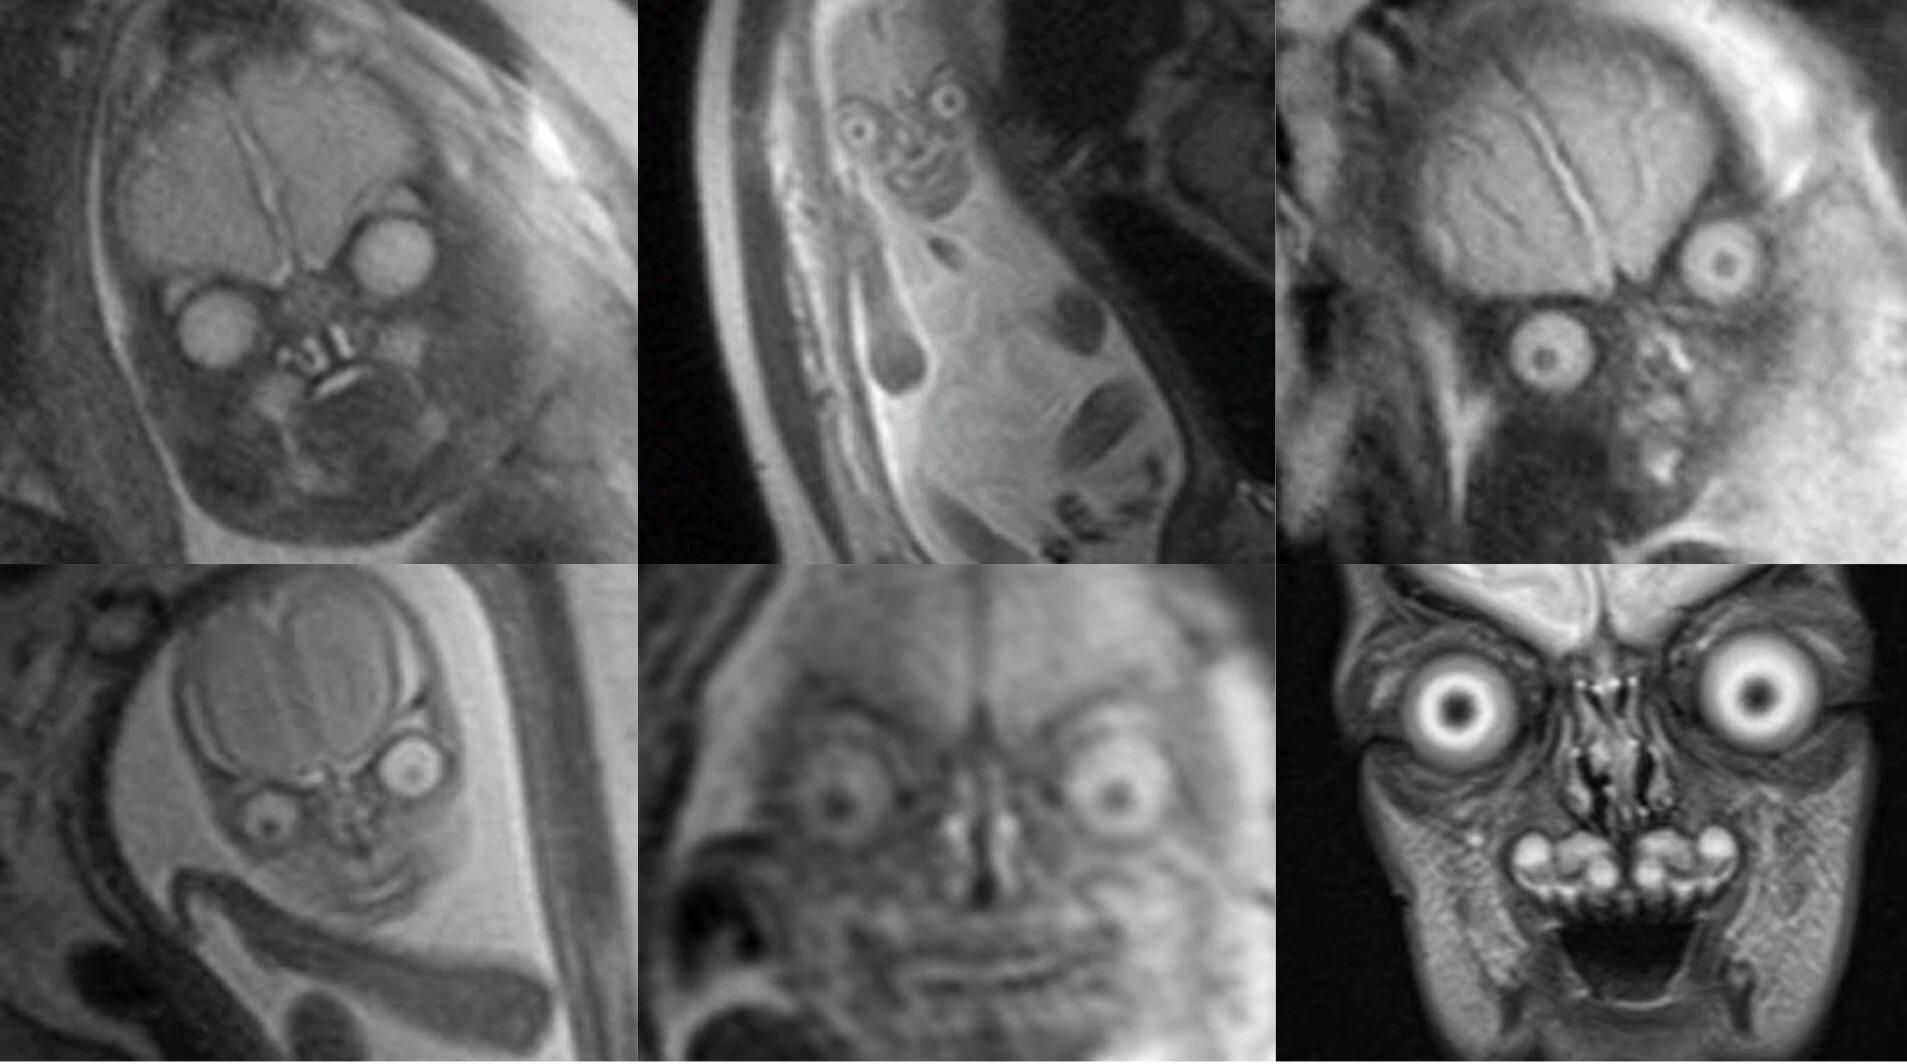

From www.reddit.com

MRI scans of babies in the womb r/oddlyterrifying When Were Baby Scans First Used According to livescience, the ultrasound machine as we know it today was first used in glasgow in 1956 — and the prototype. Ultrasound was first used for clinical purposes in 1956 in glasgow. History of the ultrasound scan. This breakthrough has profound implication in the. A brief history of the sonogram. At first, ultrasounds were primarily used for diagnostic purposes. When Were Baby Scans First Used.

From todayuknews.com

Are these aliens... or human babies? Mindboggling MRI scans of When Were Baby Scans First Used Two austrian scientists, karl dussik and his brother. At first, ultrasounds were primarily used for diagnostic purposes in areas like cardiology and urology. This breakthrough has profound implication in the. History of the ultrasound scan. Obstetrician ian donald and engineer tom brown developed the first prototype systems based on an instrument used to. It wasn't until the 1970s that ultrasounds. When Were Baby Scans First Used.